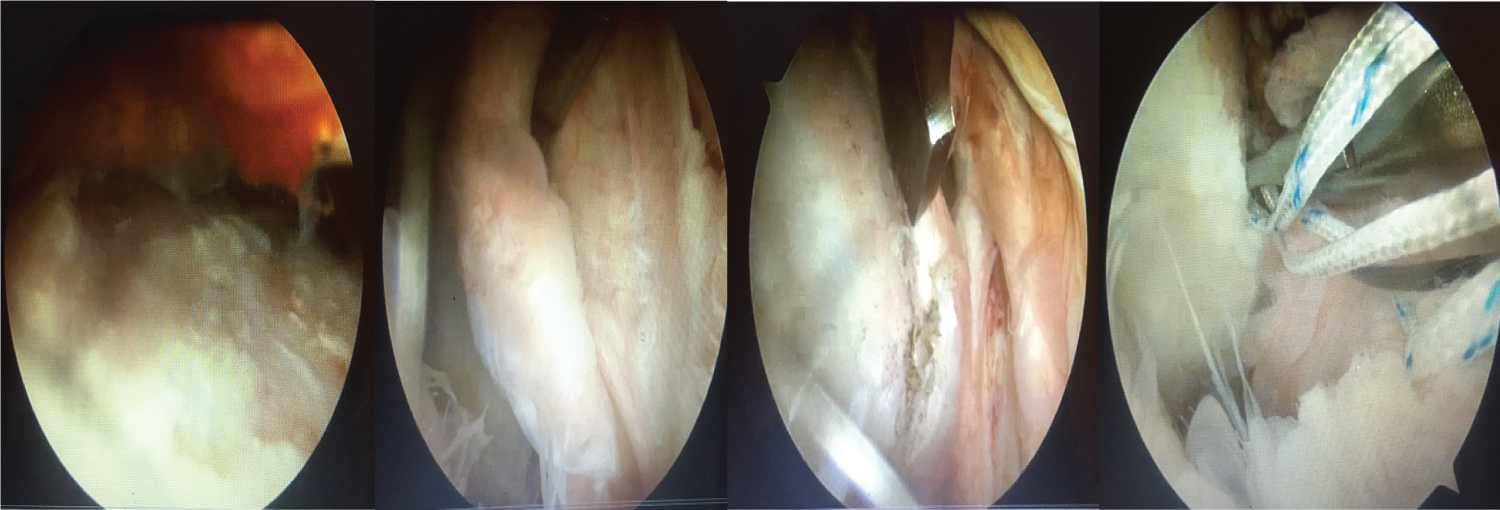

After clinico-radiological evaluation, the therapeutic decision based on the ISIS score, established between 1 and 2 for all cases, was to perform an arthroscopic BANKART. After exploration, the procedure consisted of assessing the presence of a HILL SACKS lesion, which was noncommittal in all cases, and did not require a filling procedure. The anterior-inferior labral detachment and the capsule were then fixed at the anterior glenoid rim at around 15 and 17 o'clock using metal anchors after the anteroinferior edge had been raised (Figure 2 and Figure 3). It should be noted that the patients had no associated lesions on the rest of the labrum.

Figure 2: Non-engaging Malgaine notch, Anteroinferior labral detachment, Anteroinferior glenoid rim advancement, Implantation of a metal anchor. View Figure 2